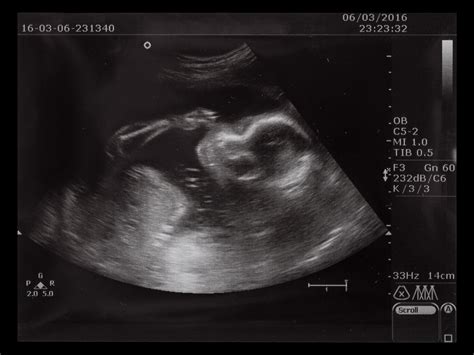

Le Misure Ecografiche: Dalla Testa al Femore

Il Diametro Biparietale (BDP) corrisponde alla misura trasversale del cranio fetale. La Circonferenza Cranica (CC) è la misura del perimetro della testa. La Circonferenza Addominale (AC) è la misura del perimetro dell'addome. La Lunghezza del Femore (FL) è la misura dell'osso della coscia. La Lunghezza dell'Omero (HL) è la misura dell'osso del braccio.

Queste misure vengono poi inserite in formule specifiche o confrontate con tabelle di riferimento per stimare il peso fetale e la sua crescita. È importante notare che la proporzione tra le diverse misure può essere altrettanto significativa quanto le misure assolute. Ad esempio, una testa e un addome grandi rispetto alla lunghezza del femore potrebbero destare preoccupazione, ma è fondamentale considerare l'andamento generale della crescita e le caratteristiche genetiche dei genitori.

Durante il primo e all’inizio del secondo trimestre, la dimensione principale da tenere sotto controllo è il valore che si ottiene misurando dalla testa fino all’osso sacro (o lunghezza vertice-sacro, Crown-Rump Lenght, CRL). La misura più affidabile (perché gravata da un errore standard percentuale più basso) è la lunghezza vertice-sacro (CRL).